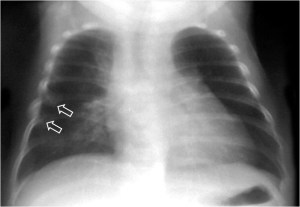

SIGNO DE LA CISURA INCOMPLETA, DE LA PSEUDOCAVIDAD O SIGNO DE LA ESPINA DE ROSA

Es un signo de derrame pleural en la cisura mayor visible en la radiografía de tórax, en un paciente con cisura mayor incompleta. Es más frecuente verlo en el lado derecho ya que en el izquierdo la silueta cardiaca puede ocultarlo.

La presencia de una zona radiotransparente perihiliar, circunscrita lateralmente por una línea curva bien marcada (flecha blanca), en cuya periferia se observan varios grados de opacidad, corresponde a la presencia de líquido en la cisura mayor incompleta. La línea curva termina en un extremo en punta (flecha roja), que estará más cercana al hilio cuanto más completa sea la cisura.

El nombre de pseudocavidad hace referencia a la radiolucencia perihiliar, mientras que el de espina de la rosa se refiere a la morfología de la opacidad, con el extremo en punta.